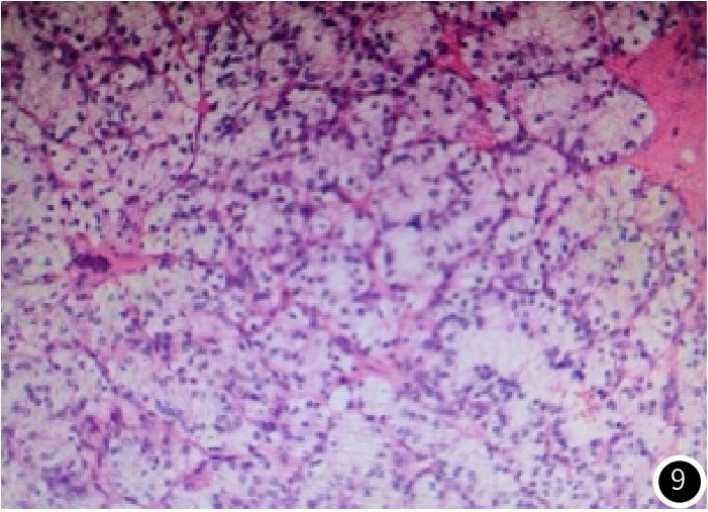

:2017年胰头结节手术探查,术中见胰头下缘约2cm×2cm结节,质中,色偏黄,界尚清。镜检:瘤细胞呈巢状排列,细胞为圆形或卵圆形,胞质丰富且透亮。免疫组织化学:CA9(+++)、Pax-8(++)、Vimentin(++)、CK19(局灶+)、CK7(-)、F504s(-)、TFE3(-)、CD99(-)、Syn(-),Ki-67约20%+。病理诊断:肾透明细胞癌胰头转移(图9)。

图9 胰头占位术后病理(HE×200)示瘤细胞呈巢状排列,细胞呈圆形或卵圆形,胞质丰富、透亮。